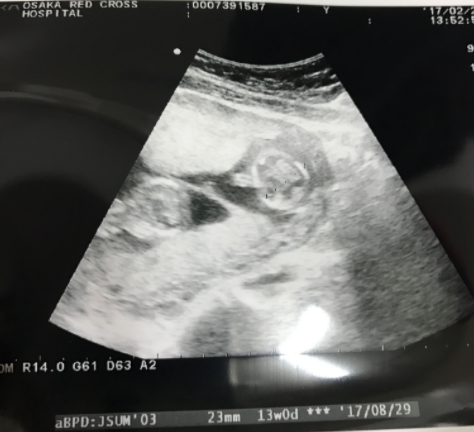

13週1日(13w1d・女の子)|y twin mam さん(36歳)

画像は悪いですが、双子ちゃんが一緒に写った貴重なエコー写真です♪ この頃はつわりがあり、出血もありで、仕事をしながら不安な日々を過ごしてました。

今は34週に入りましたが、赤ちゃんたちはずっと問題なくすくすくと育ってくれています。 待望の赤ちゃんたち。無事に産まれてきてくれるのが楽しみです!